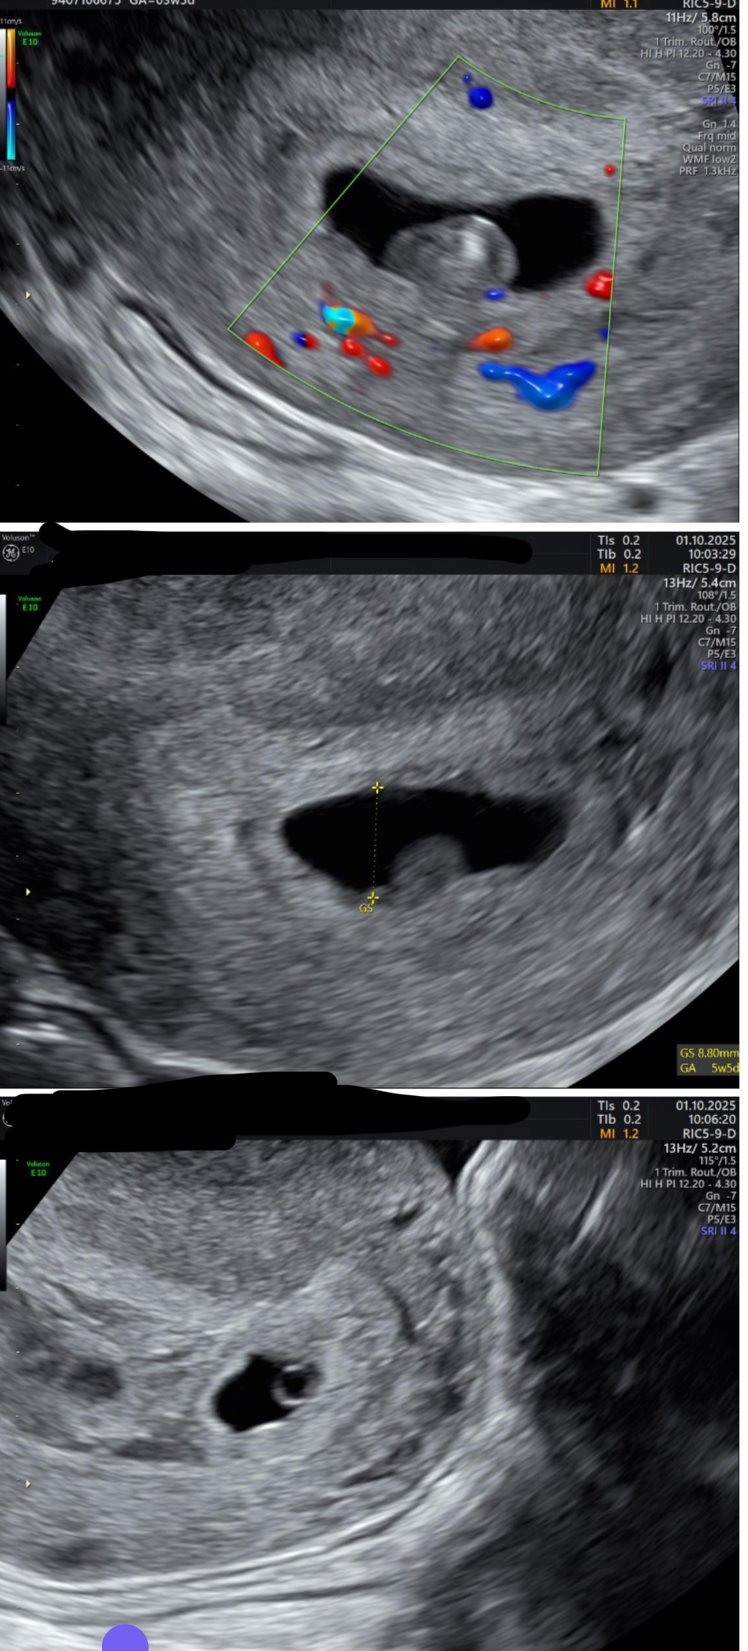

Здравейте! Днес бях на преглед (5+5 според дата на трансфер или 5+1 според ПМЦ). След трансфер съм на два 5-дневни ембриона. На ехографа се видя, че двата ембриона имат 3 дена разминаване спрямо размерите, но повече ме притеснява как изглежда по-големият ембрион.

Лекарката не беше много сигурна на какво ѝ прилича, но предположи вариант - хематом, който скрива жълтъчно мехурче и ембриона и всичко изглежда като една маса. Пусна доплера и се видя, че има активен кръвоток към сака и че според нея има ембрион.

Последната снимка е на второто ембрионче, което е по-малко, но изглежда с правилни размери.

Някоя в подобна ситуация да в била? Всякакви мнения ще са ми полезни.